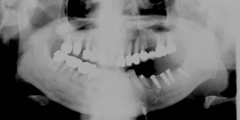

吉本歯科医院では、口内写真とパノラマレントゲンを撮影し、まずは顎の骨の状態まで詳しく確認しました。

写真(2)パノラマレントゲン写真

院長の吉本の診断は、次の3つでした。

・入れ歯では合わない、噛めないのは当たり前

・合わない入れ歯を入れているために骨がどんどん退縮していっている

・入れ歯を入れたり入れなかったりするため、歯並びがどんどん崩れだしている